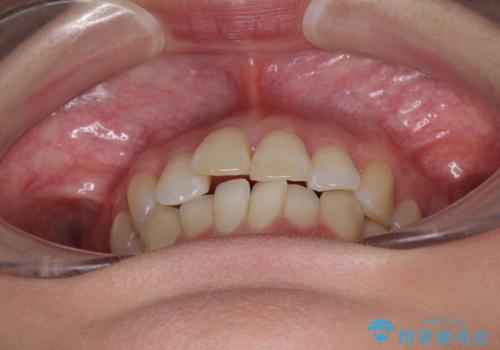

- 奥歯の咬み合わせを気にして来院された患者様です。

上顎骨の幅が下顎骨よりも小さいので、拡大装置により骨幅を広げて上下関係を改善し、その後インビザラインにて歯並びを整えることとしました。

上下の骨幅を改善したことで、スムーズに歯列矯正を行うことができました。

奥歯の咬み合わせを改善する必要があったため、治療は長期化しましたが、きっちりと仕上げることができました。